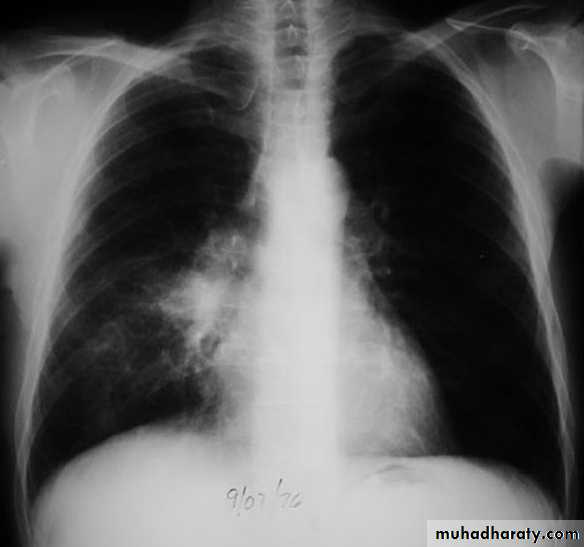

Mycoplasma pneumonia. A 35 year old man presents with nonproductive cough and fever